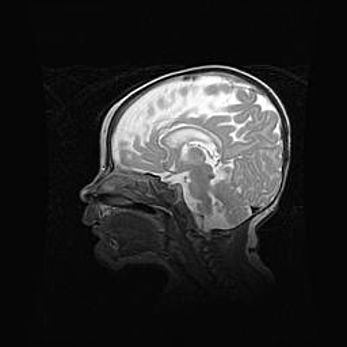

Мальформация Денди-Уокера. Киста задней черепной ямки.

Агенезия мозолистого тела.

Возраст: 2,5 месяца

Вес: 2420 г

Пол: женский

Окружность головы: 37 см

Срок гестации: 32 недели

Мальформация Денди—Уокера — редкий вид патологии ЦНС, представляющий собой врожденный порок развития каудального отдела ствола и червя мозжечка, ведущий к неполному раскрытию срединной (Мажанди) и латеральных (Лушка) апертур IV желудочка мозга. Для этогно синдрома характерна триада симптомов: гипотрофия червя мозжечка и/или полушарий мозжечка, кисты задней черепной ямки, гидроцефалия различной степени. В 70% случаев порок сочетается и с другими аномалиями головного мозга, в частности с агенезией мозолистого тела.